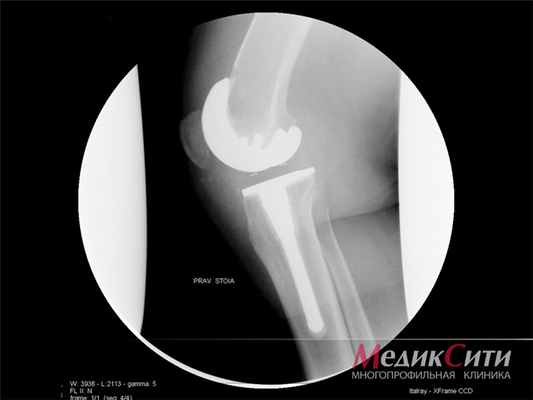

На поздних стадиях заболевания при неадекватной либо поздней терапии, при агрессивном течении болезни иногда необходимы хирургические методы лечения, восстанавливающие функцию конечностей. Видами хирургической коррекции при РА являются - синовэктомия (удаление синовиальной оболочки пораженного сустава), реконструктивные операции на костях, связках, сухожилиях крупных и мелких суставов (пластика), а также эндопротезирование.

- эндопротезирование – замена пораженного сустава;